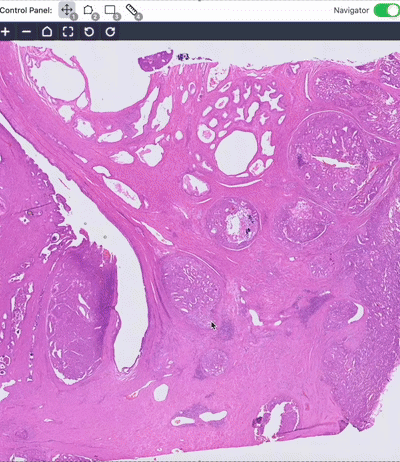

1. Foundation Model for Pathology

Pathology is medicine's ground truth. We train AI models with vision, language, and knowledge to improve machine understanding of pathology.

A visual–language foundation model for pathology image analysis using medical Twitter

Zhi Huang†, Federico Bianchi†, Mert Yuksekgonul, Thomas J. Montine, James Zou (†: Equal contribution)

Nature Medicine (2023), cover article

Artificial Intelligence Reveals Features Associated with Breast Cancer Neoadjuvant Chemotherapy Responses from Multi-stain Histopathologic Images

Zhi Huang, et al.

NPJ Precision Oncology (2023)

✨ AI-powered prediction of breast cancer treatment outcomes from H&E and IHC.